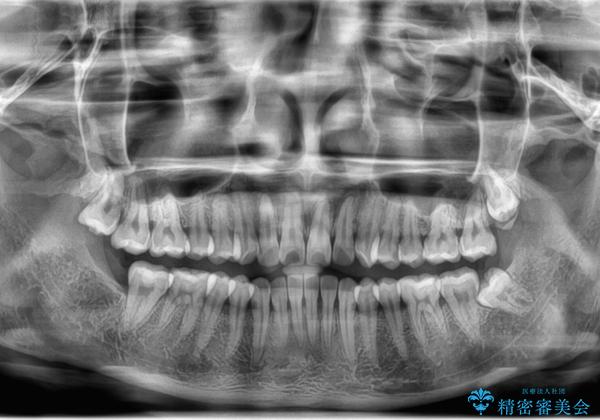

左下の親知らずが腫れた感じがする。

- 左下親知らずが腫れてる感じがして痛いとの事で来院。

抜歯を希望されたので抜歯術を行いました。

親知らずを長年放置すると手前の歯が虫歯になるリスクがあがります。

虫歯になる前に親知らずは抜歯することをお勧めします。